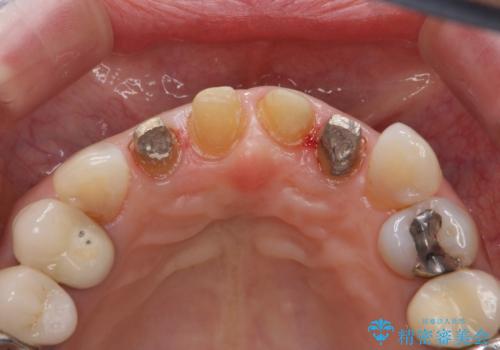

50代女性 前歯のつめものがとれた これを機に前歯をきれいにしたい

- 前歯の詰め物が頻繁に外れるとのことで来院。

これを機にセラミックでかぶせて、前歯の歯並びも良くしたいとのことでした。

左上の前歯のみねじれが大きいため、歯の位置をひっこめたかぶせものにするために、神経の治療を行っています。

- 59.5万円 (オフィスホワイトニング 3万円、ジルコニアクラウン スタンダード 10万円×4本、仮歯 1万円×4本、精密根管治療(左上1)6万円×1本、ファイバーコア 2万円×1本)費用は治療当時の料金となります